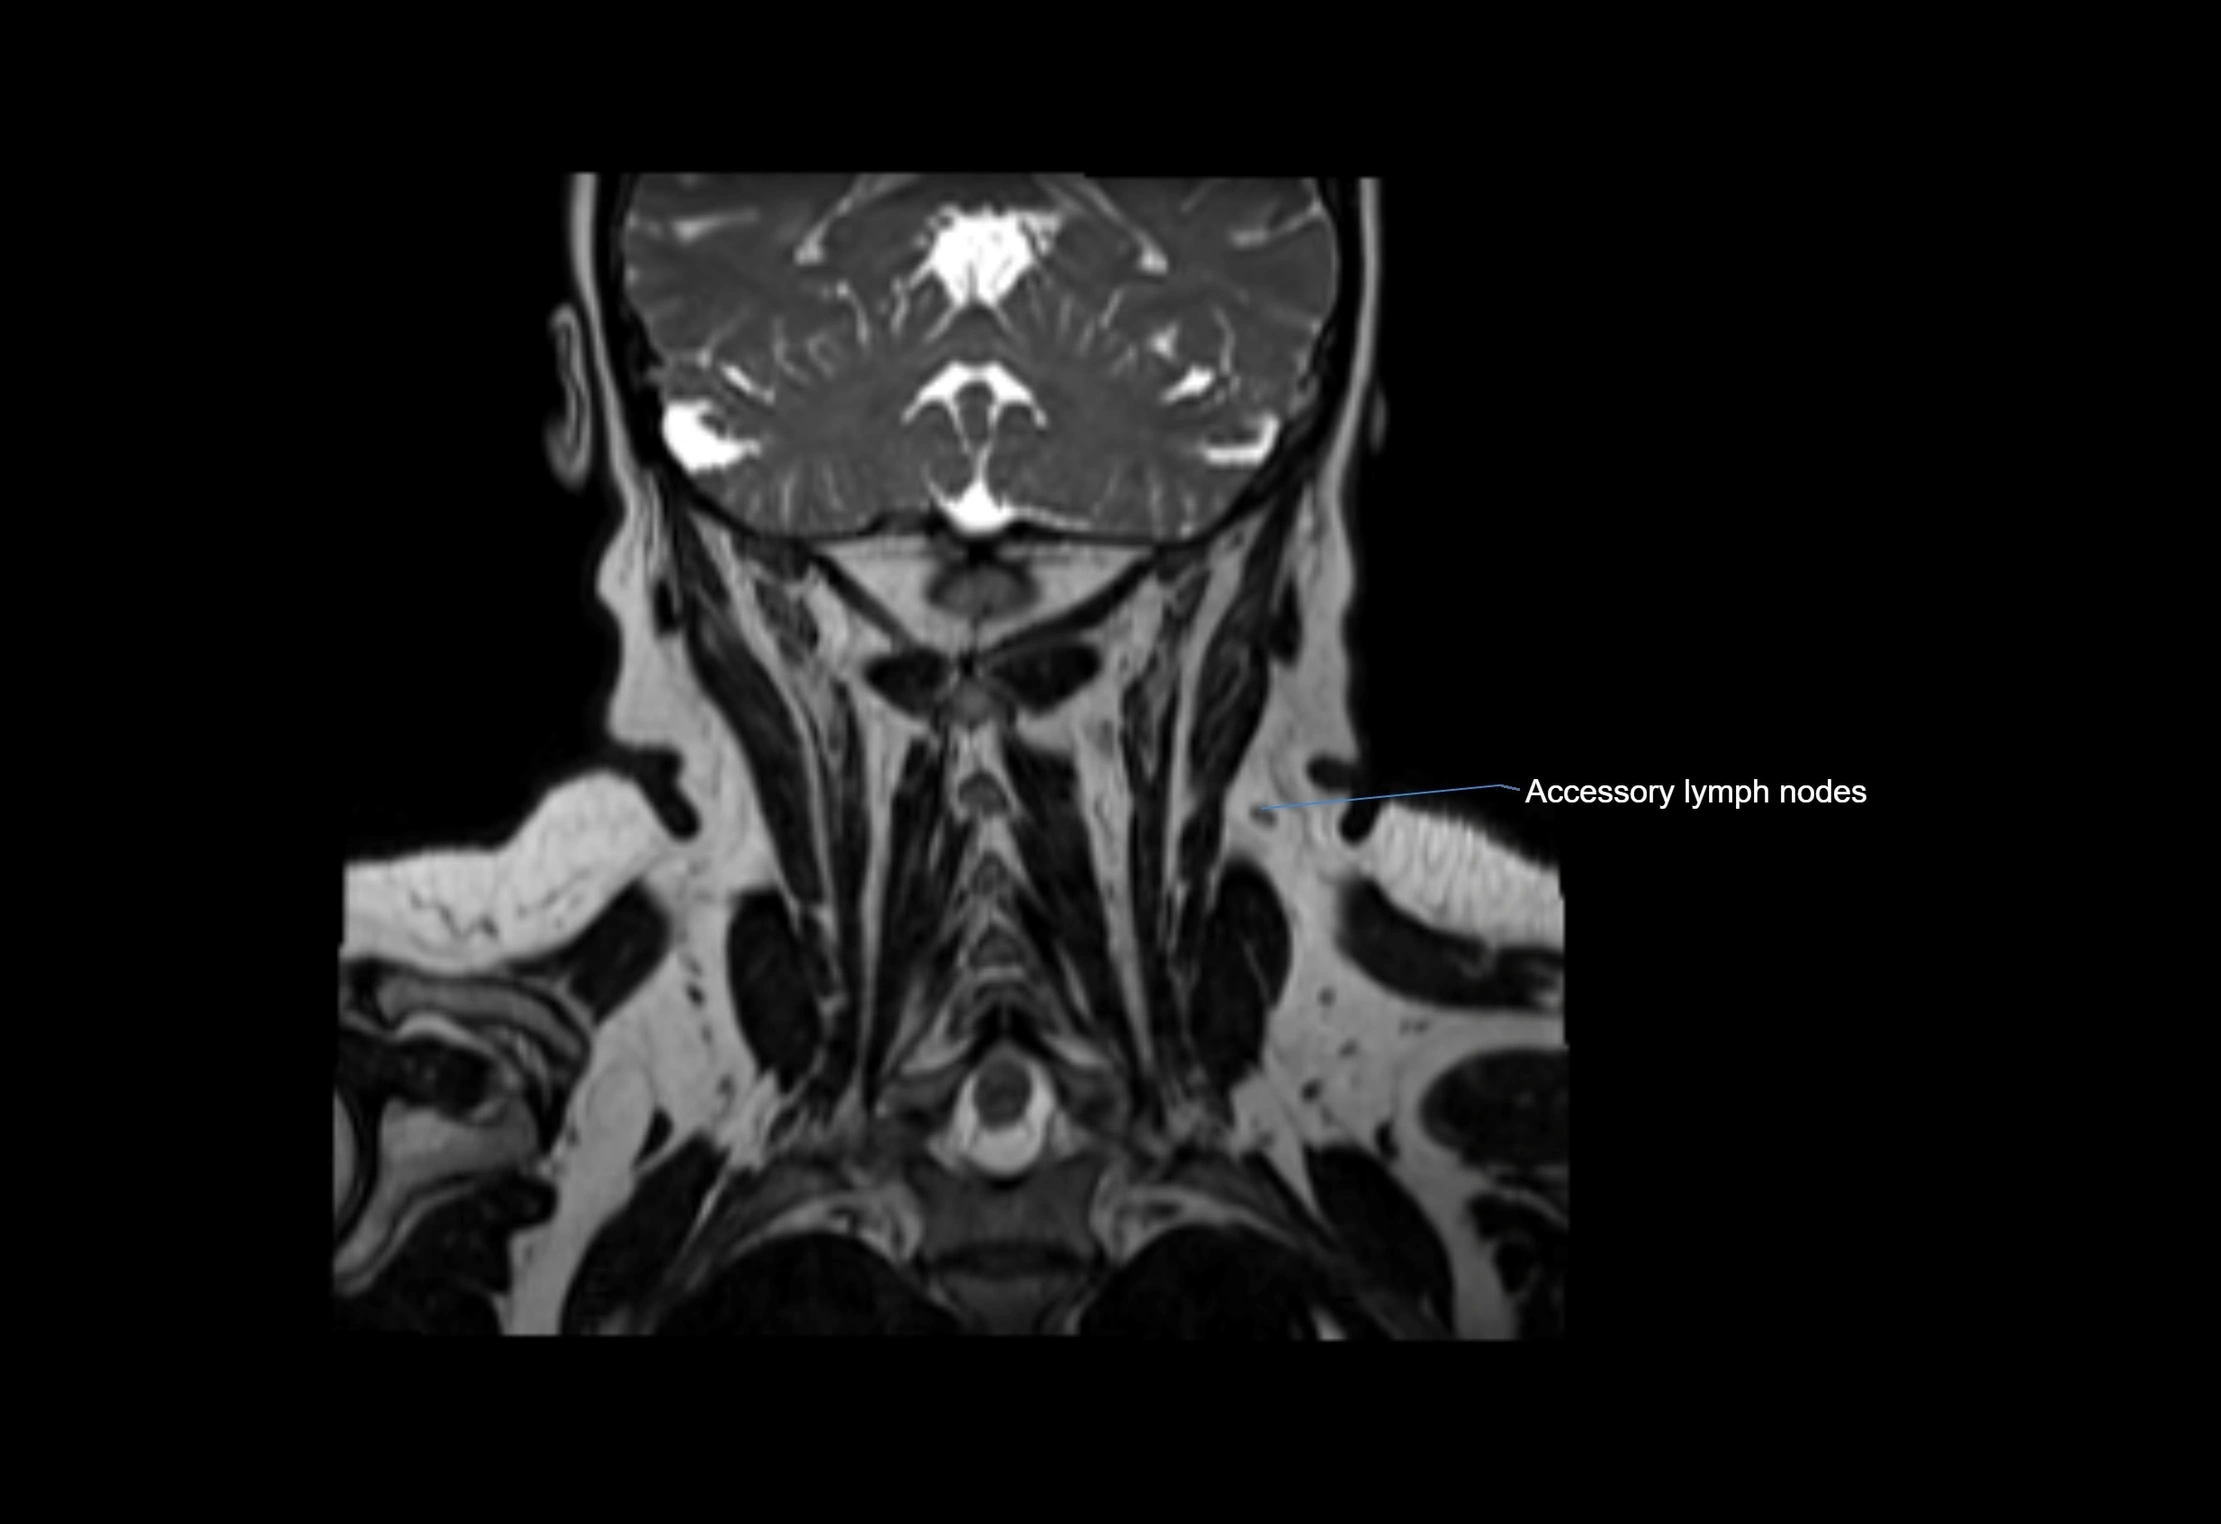

Accessory lymph nodes

Accessory lymph nodes are small, secondary lymph nodes located along the main facial and cervical lymphatic chains, often adjacent to primary lymph nodes, such as preauricular, submandibular, or occipital nodes. They are typically less than 5 mm in diameter, embedded within subcutaneous fat or connective tissue, and may be variable in number and location. These nodes provide additional filtration and immune surveillance for lymph collected from the face, scalp, and neck regions. Accessory lymph nodes are usually non-palpable in healthy individuals but may enlarge in response to infection, inflammation, or metastasis, making them clinically significant.

Location

• Found along primary lymph node chains, including preauricular, submandibular, parotid, and occipital regions

• Embedded in subcutaneous fat or superficial fascia, often lateral or posterior to primary nodes

• Variable in number; may occur unilaterally or bilaterally, depending on individual anatomy

MRI Appearance

T2-weighted images:

• Nodes show intermediate signal, with surrounding fat bright

• Useful for detecting edema, inflammation, or infiltration

• Fatty hilum may appear slightly hyperintense relative to cortex

STIR (Short Tau Inversion Recovery):

• Fat suppression enhances visualization of edematous or pathological nodes

• Normal nodes appear low to intermediate signal, while inflamed or metastatic nodes appear hyperintense

• Useful for detecting subtle lymphadenopathy or early pathology

MRI images

image